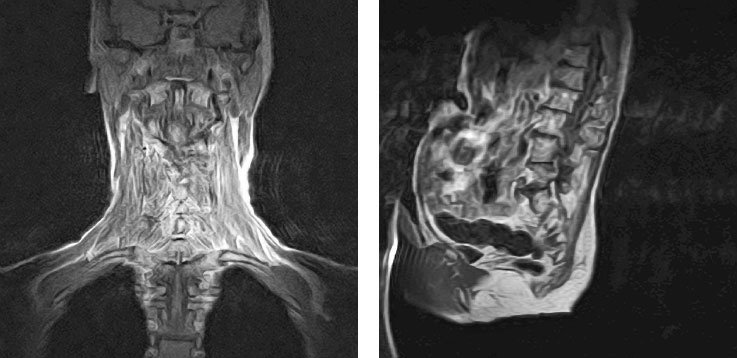

Рисунок 33. Мышцы спины стимулируют практически все точки шейных позвонков (слева), в то время как поясничный отдел сохраняет полностью вертикальное положение и не подвергается никакому риску даже при скручивании на 90 градусов, как в позе ардха-матсиендрасана (справа).